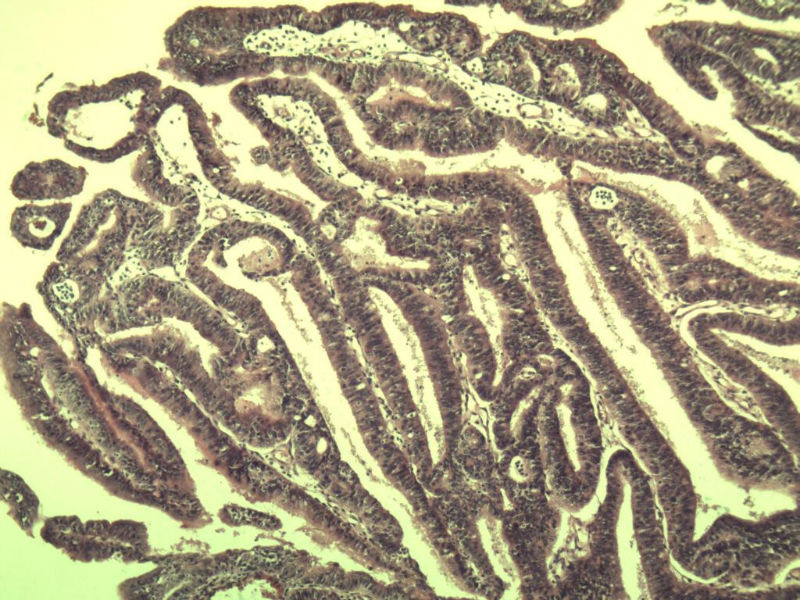

女 32岁 不规则阴道流血 一年  请各位老师看看 谢谢了

遵义医学院附属医院会诊结果    "复杂性增生伴非典型性 "

补充一下病史 病人10个月前因月经不规则行诊刮 诊断非典型性增生  上了曼月乐避孕环(好像是缓慢释放孕激素的那种),         都用激素治疗大半年了 还是这个样子 我还是觉得是癌  只有追踪一下以后病人的情况吧

高分化子宫内膜样癌

非典型复杂性子宫内膜增生,应了解雌孕激素情况。

子宫内膜复杂性非典型性增生,局灶区间质肉芽样(图5)及蜕膜样变,不够癌,建议临床查激素水平并追踪。

从照片看,没看到浸润的地方,我考虑是子宫内膜重度不典型增生。